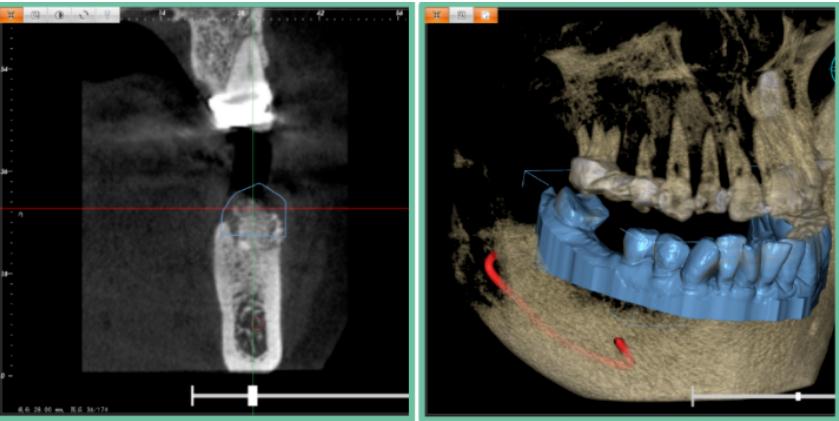

在精瓷义齿FC种植供应链平台下单后,在FC Implant导板软件进牙模与CSCT三维进行数据处理,高精度还原病例患者口内情况。数据传输完毕后,能够快速保存至平台,极大地缩减了取模流程。

以数据为依据,设计并规划最为精准的种植体方案,确认好虚拟种植体在病例患者牙槽骨内的最佳位置,提前做好预判,为实际手术进行引导。